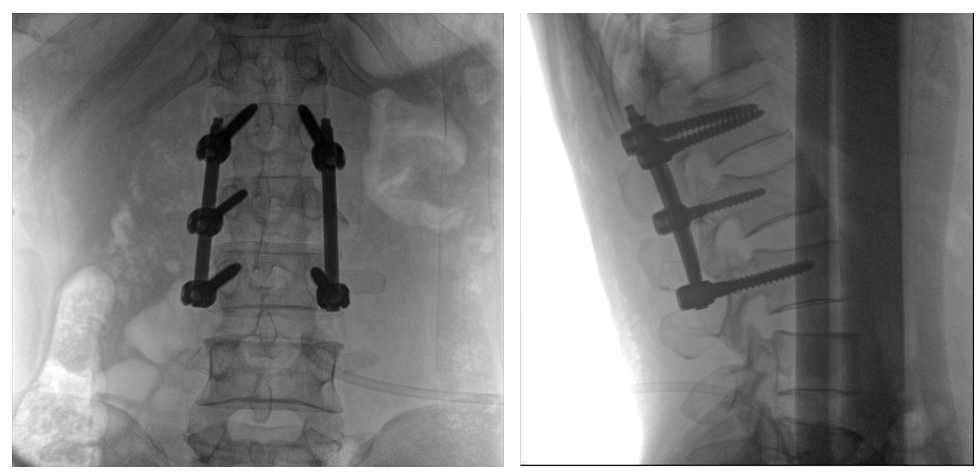

普愛醫療PLX119C大平板一體式C形臂采用30CM×30CM的平板探測器,在脊柱和長骨骨折等骨科手術治療中,獲取更大視野、更清晰的骨折部位圖像,能夠有助于醫生在術中及時了解和評估骨折部位的對位、對線情況,且能進行長度和角度測量,為進一步提高手術質量提供強有力的支持。